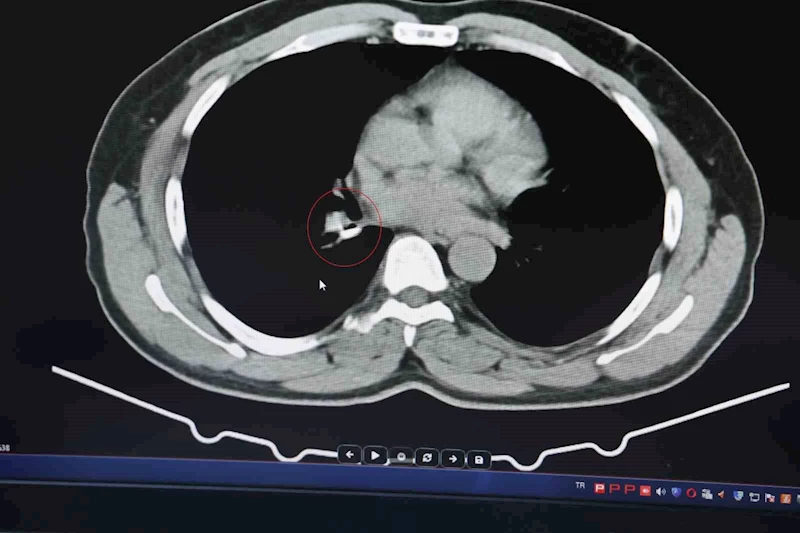

1,5 yıldır astım tanısından sonra tedaviler almaya başlayan İ.U., Prof. Dr. Abdurrahman Şenyiğit’in yanına geldiğinde yapılan tetkiklerde gerçek bambaşka çıktı. Yapılan tomografi ve bronskokopi işlemlerinde akciğere yerleşen maddenin yutulan silikon olduğu belirlendi. Silikonun çıkartılmasıyla hastanın tarifine göre şikayetlerinin ortadan kalktığı belirtildi.

Şenyiğit, o maddenin zamanla akciğer yapısının özelliğini aldığını ve orada yabancı bir madde olarak kaldığına değinerek, "Hastamıza maalesef 2 yıldan beri astım tanısı konulmuş ve sürekli tedavi verilmiştir. Hasta bize geldiği zaman yapılan tomografide sağ akciğer ana bronşun distalinde şüpheli lezyon gördük. Uyguladığımız bronskokopide yabancı maddenin silikon olduğunu tespit ettik. Onu çıkardıktan sonra da hastada bir rahatlama meydana geldi" dedi.